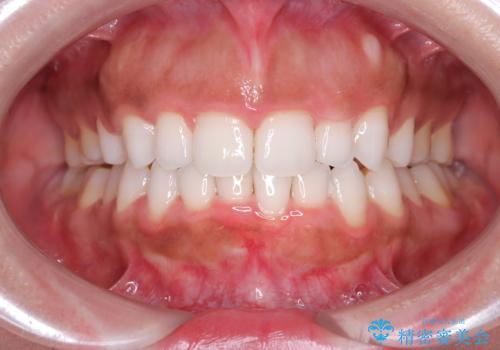

前歯の出っ張りとガタつきを改善

- 「前歯が出ていて並びも悪いのが気になる」との主訴で来院されました。診察の結果、上顎前歯の前突と中等度の叢生(ガタつき)が認められ、歯がきれいに並ぶスペースが不足していました。横顔のバランスと歯並びの両方を整えるため、上顎の左右の第一小臼歯2本を抜歯し、前歯を内側に下げながら歯列全体を整える治療計画を立てました。

治療はインビザラインによって進め、抜歯スペースを使って前歯を内側に引き込みながら、歯のガタつきも順に整えていきました。初期の段階で前歯の見た目が大きく変わり、患者さんにも「印象が柔らかくなった」と非常に喜んでいただけました。